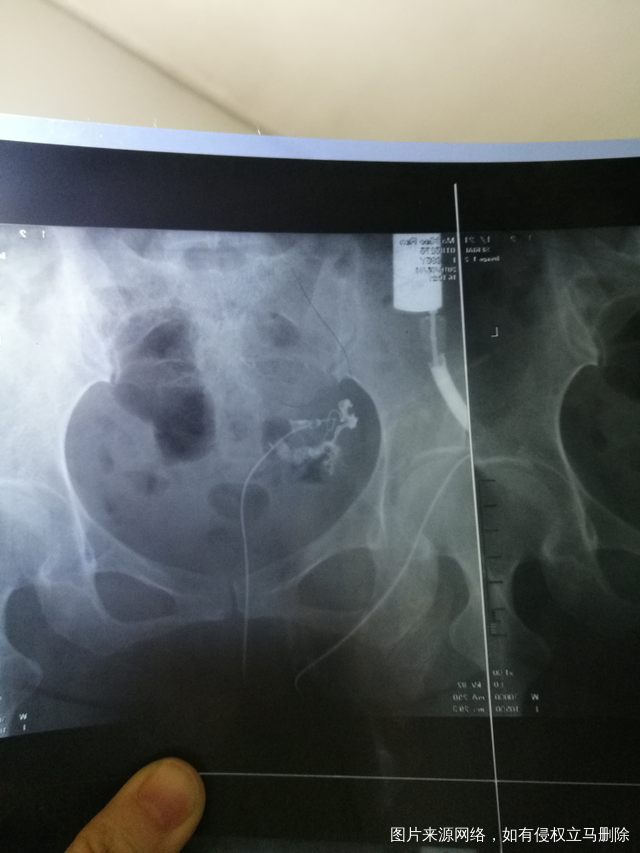

做照影左边输卵管堵塞但没说明是属于哪一种,可以治吗